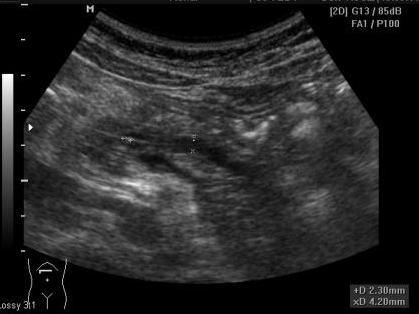

На момент осмотра пациентку ничего не беспокоит. В моче диастаза 3300.

Размеры поджелудочной:16мм -11мм-17мм

Я вынесла "хронический кальцифицирующий панкреатит", а о расширенном протоке с камнем написала и подчеркнула в описании, снимки приложила.

Сегодня девочка пришла на плановое УЗИ:

В вирсунговом протоке может быть слизистая пробка, которая может выглядеть почти как конкремент.

Но такое бывает крайне редко.